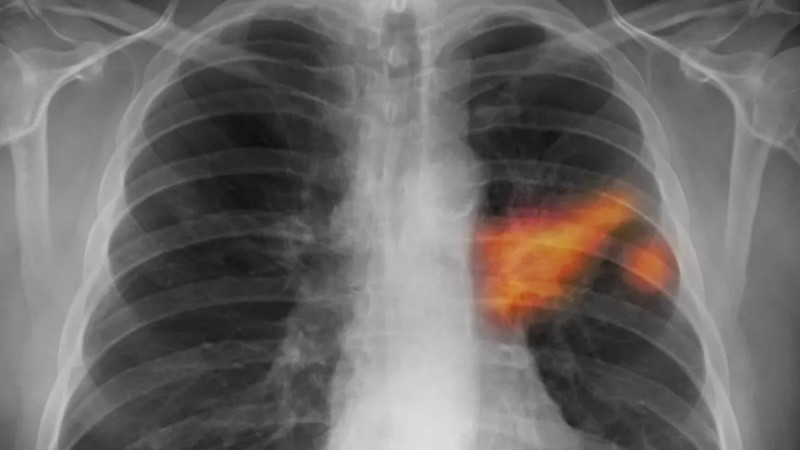

Nová studie vědců z University of Virginia Health System ukazuje, že prodělané těžké virové infekce dýchacích cest, jako covid-19 nebo chřipka, mohou zvyšovat riziko vzniku rakoviny plic, a to až o 1,24násobně, což podtrhuje důležitost sledování pacientů po vážných respiračních onemocněních stejně jako rizikových kuřáků. #rakovinaplic #covid19 #zdravotnipeci

Výzkum z University of Virginia Health System ukazuje, že těžké respirační virózy mohou trvale narušit imunitní odpověď v plicích, což zvyšuje riziko vzniku rakoviny plic, s pozitivním zjištěním, že očkování může těmto nebezpečným změnám zabránit. #rakovina #prevence #zánět

Těžký průběh respiračních viróz může zvýšit riziko rakoviny plic - Metro.cz

Zánět, který nahrává nádorům Tento překvapivý a zároveň varovný objev nedávno učinil tým výzkumníků z americké University of Virginia Health System (UVA).